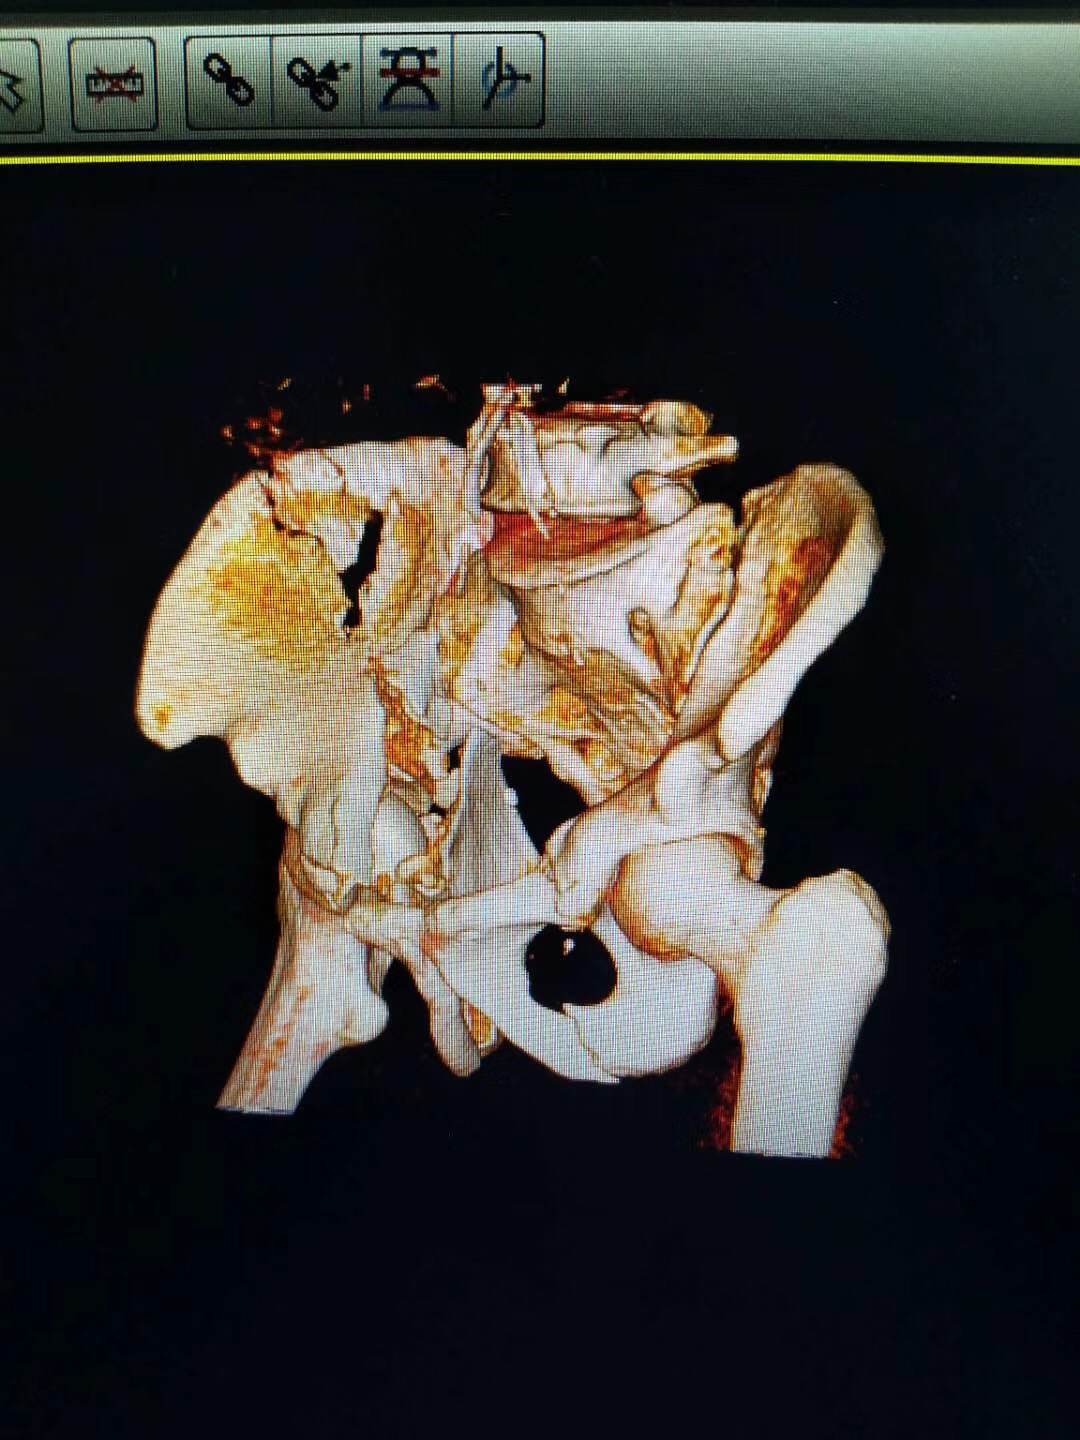

河南省安陽市人民醫院骨三科,接診一位52歲并患者,診斷為骨盆粉碎性骨折。我司收到影像數據后通過3D打印技術制作出3D打印病理模型,配合院方手術方案:切開復位內固定術。

3D打印病變骨盆模型

\